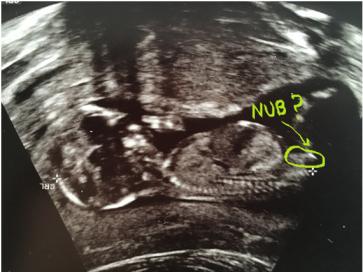

skull theory??

Attachment 35578

The nub theory?